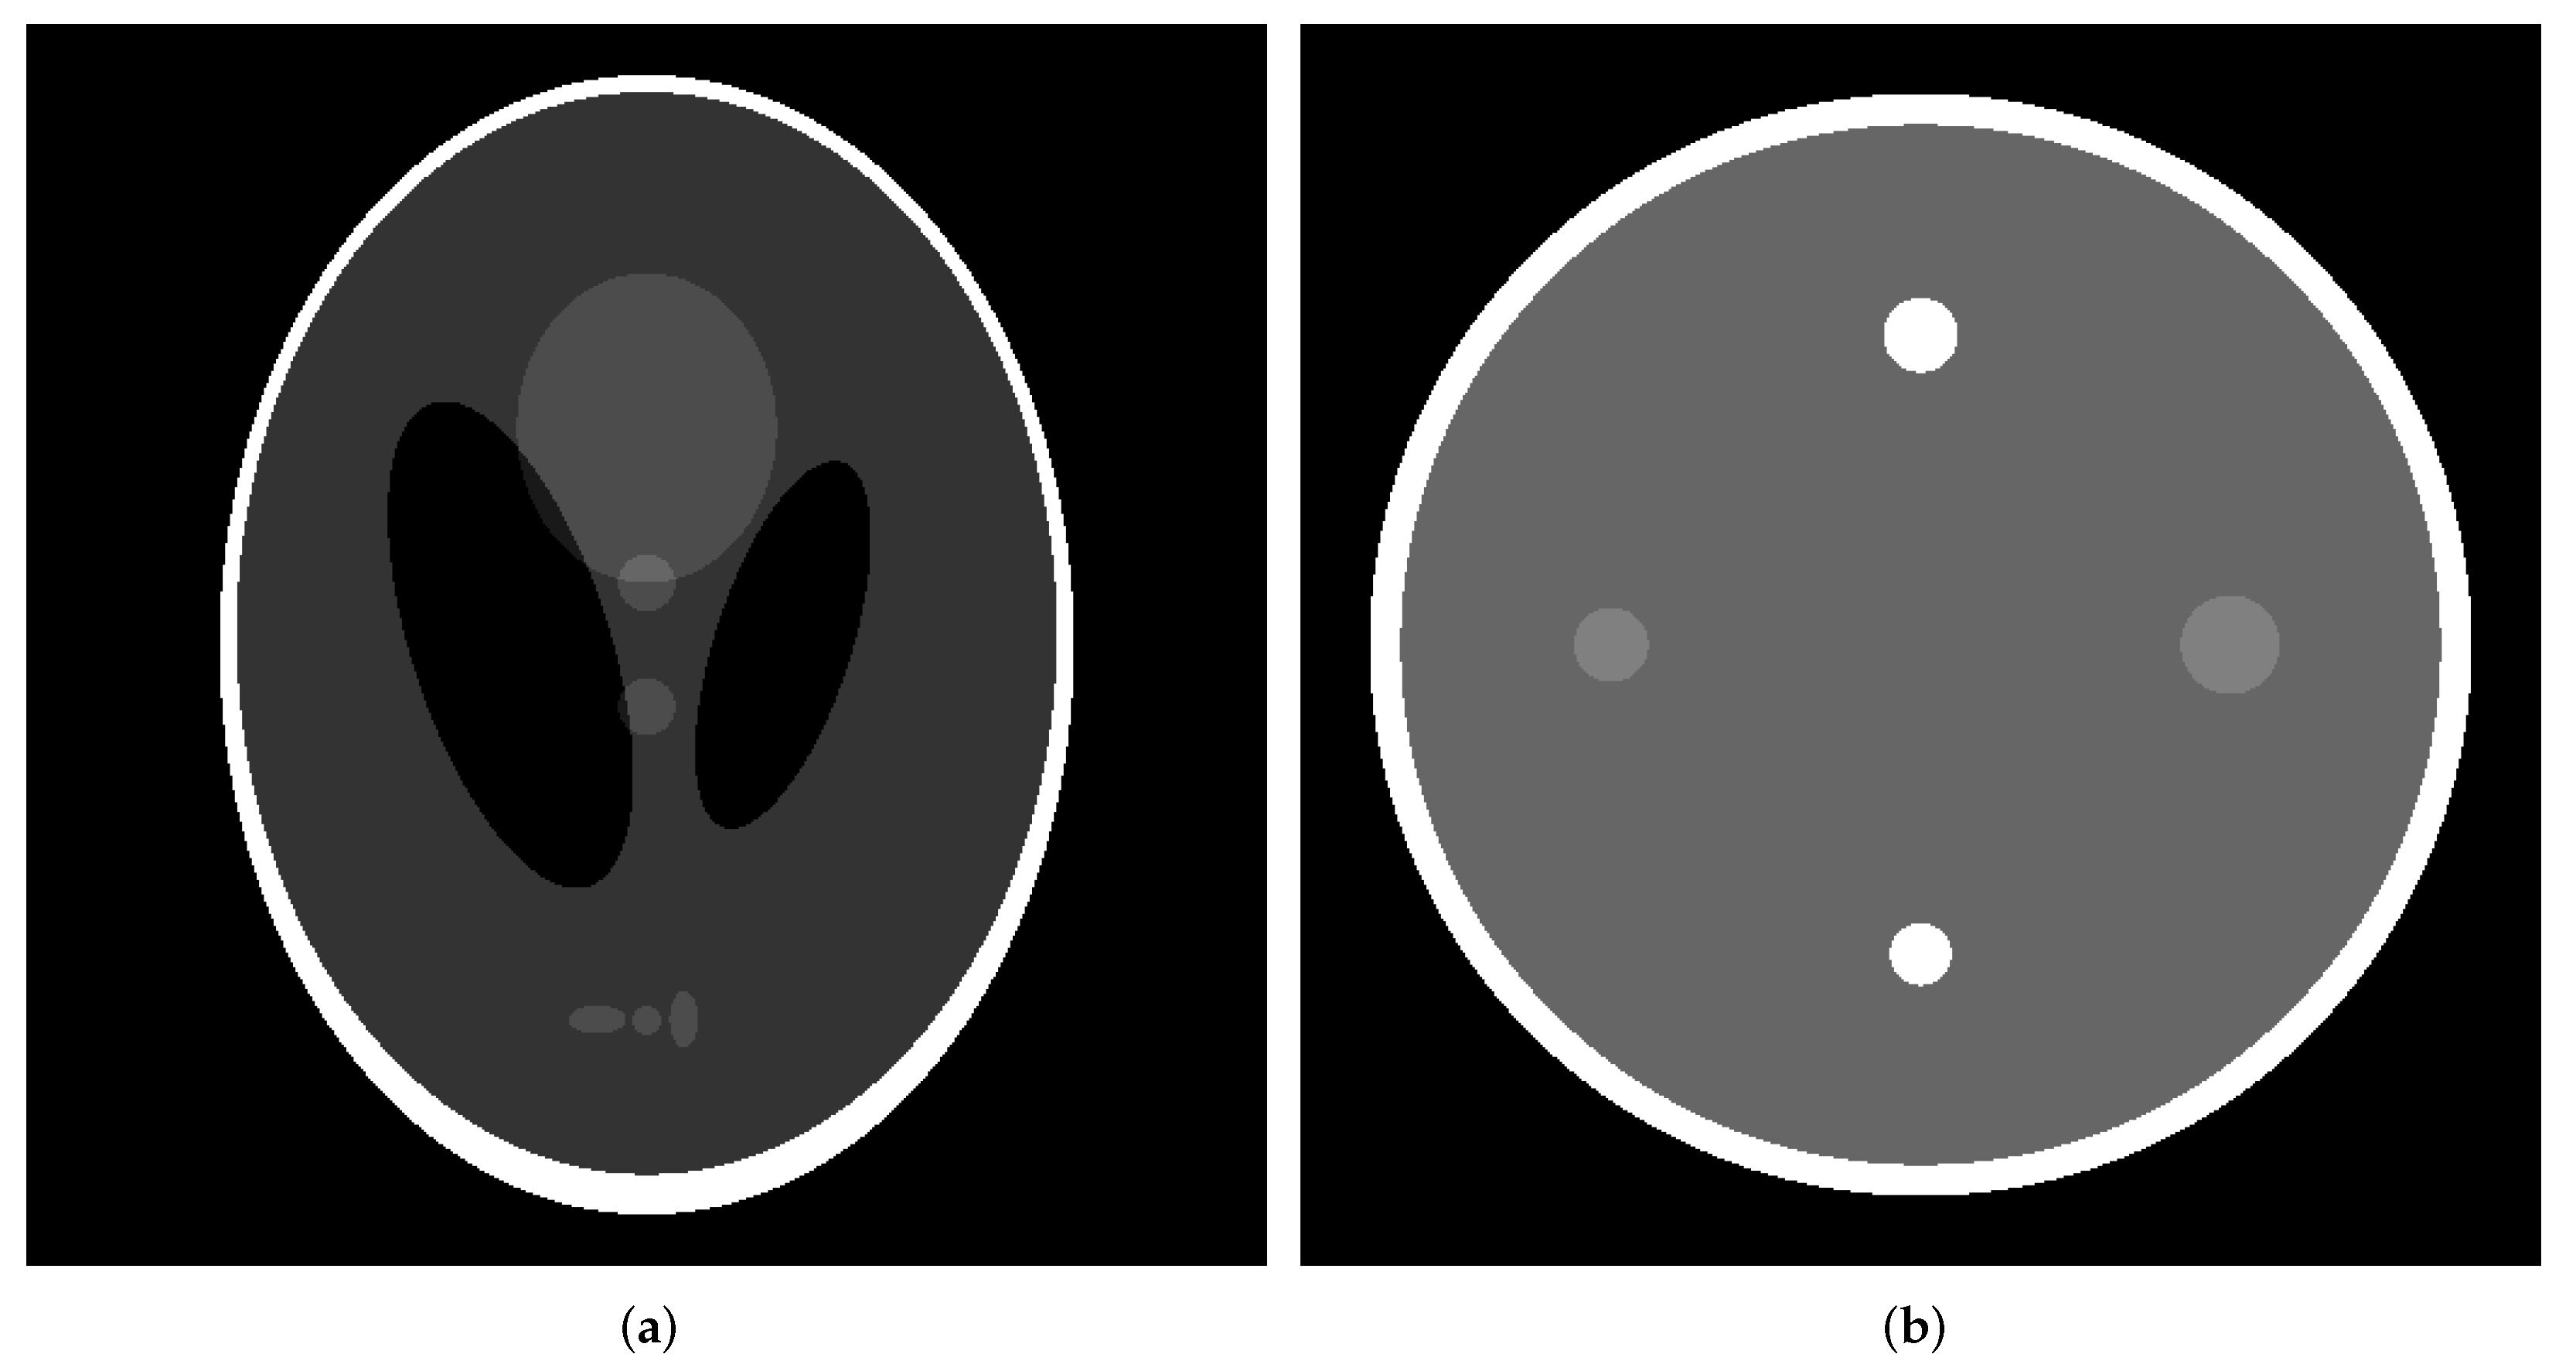

3.1. Numerical Phantom